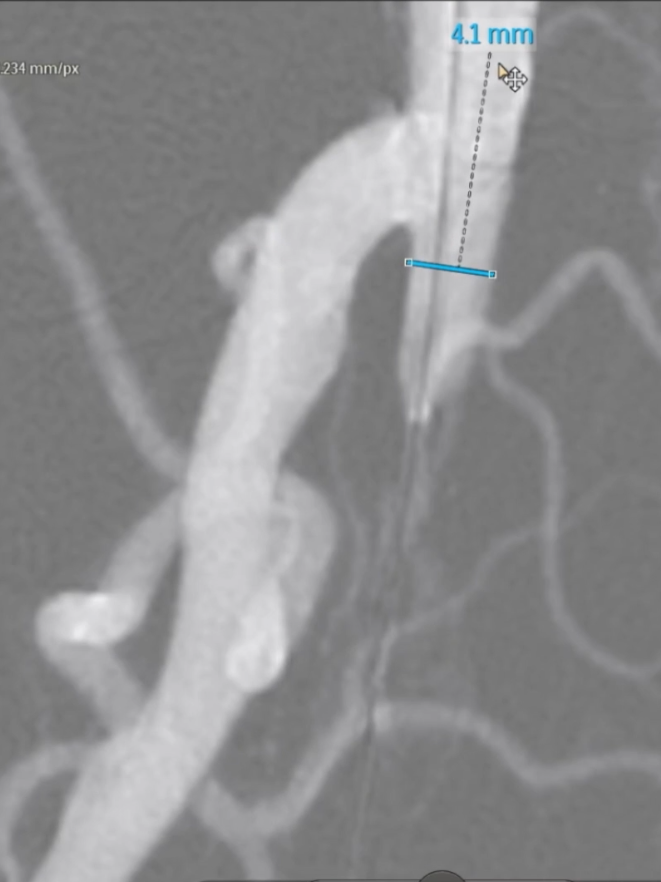

治疗模式:因股腘动脉直径<4.5mm,选择DCB(药物涂层球囊)+BMS(裸金属支架)联合方案;

支架选择:在DCB扩张导管进行管腔准备后,植入2枚5mm INNOVA支架,其优势在于尾端定位精准,尤其适合累及开口或分叉的病变。